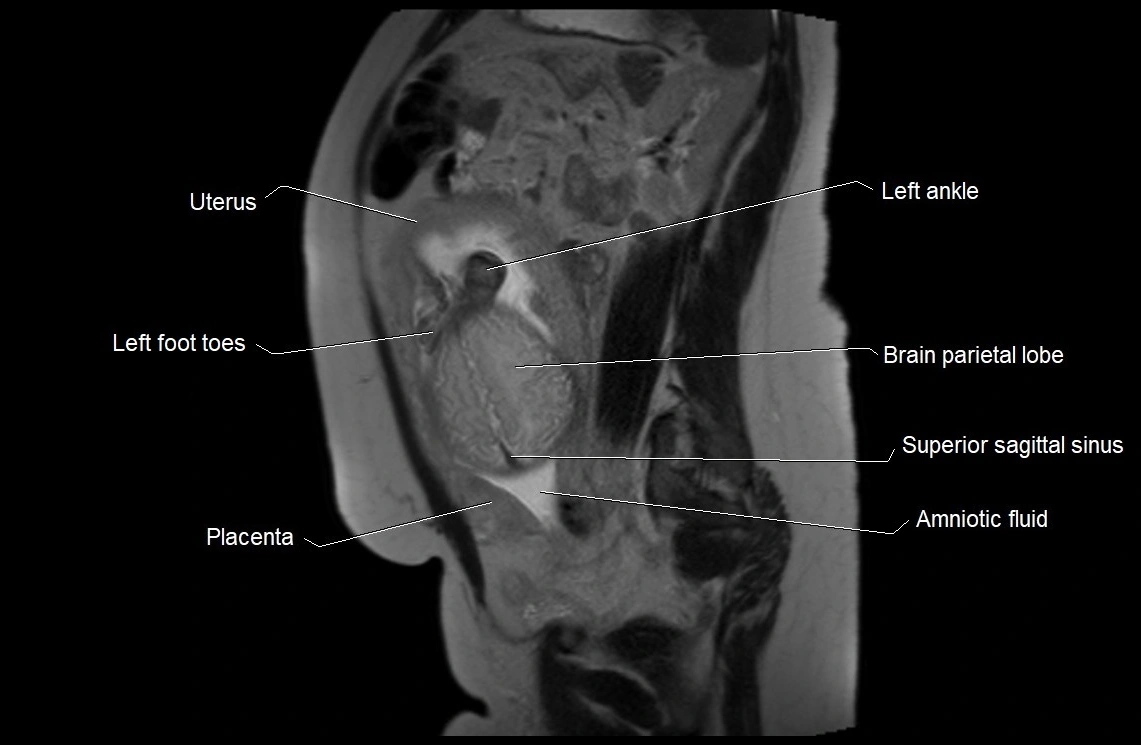

MRI Appearance

T2 HASTE (T2 GRE):

• Amniotic fluid shows very bright hyperintense signal

• Provides natural contrast against fetus and placenta

• Small particles (vernix) may appear as scattered hypointense foci within bright fluid